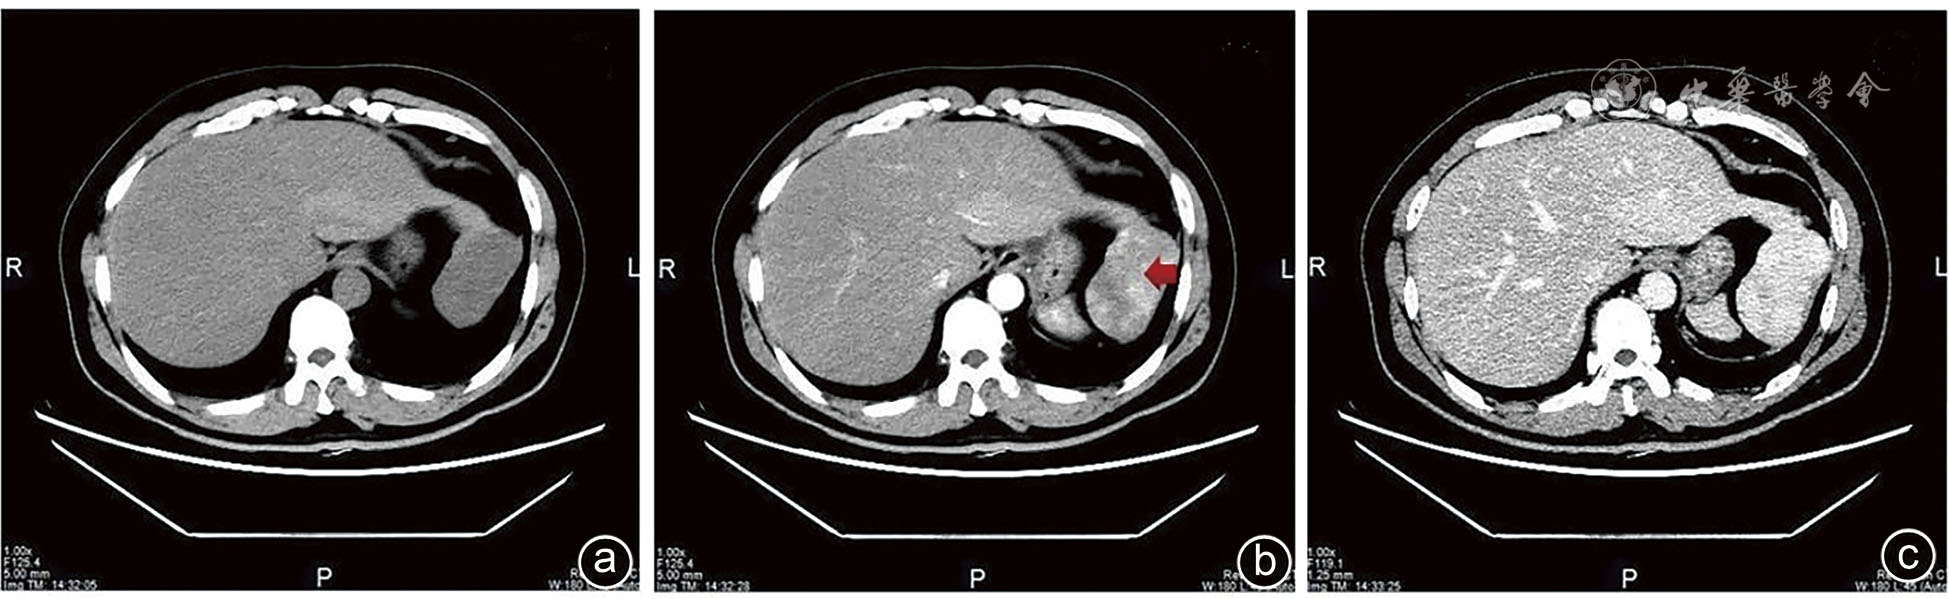

Hu N, Yan G, Tang M, et al. CT-based methods for assessment of metabolic dysfunction associated with fatty liver disease[J]. Eur Radiol Exp, 2023, 7(1): 72. DOI: 10.1186/s41747-023-00387-0.

|